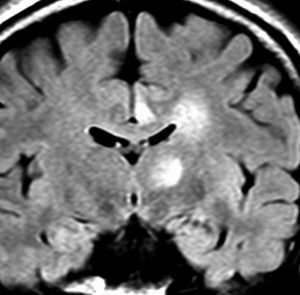

anaplastic astrocytoma,IDH-wildtype IDH 野生型

- ものすごく広い領域に広がっているものをグリオマトーシス gliomatosisといいます

無症状で発見された若年成人の左前頭葉グリオーマです。ガドリニウム(右側)では全く増強されません。手術で全摘出しました。組織像は退形成性星細胞腫でした。壊死も血管内皮増生,多核巨細胞なし,核の腫大,形不整,多形成あり,免疫組織染色とシークエンスともにIDH野生型,1p/19q共欠失なし,MIB-1染色率 10%,nuclearATRX欠失。

この例を,グレード3とするかグレード4とするかの定義はありません。

膠芽腫グレード4に準じた治療を行いました。拡大局所50Gy/25fr, 局所10Gy/5frとテモゾロマイド併用の初期治療とテモゾロマイド維持療法2年間でした。

7年後のMRIには再発はありませんでした。

振り返って見れば,この例はIDH野生型だけど,きっと星細胞腫グレード3だったんでしょう。